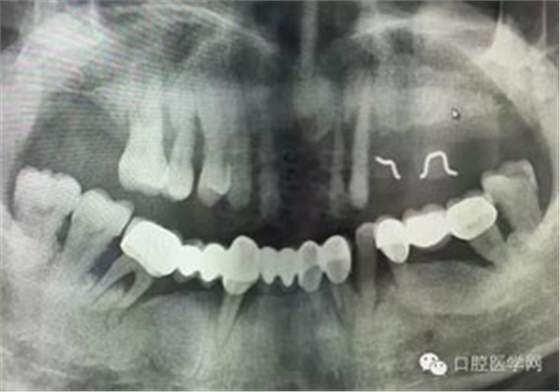

病例1:患者迫切希望保留自己的這一顆牙齒,根尖周陰影比較大,二度松動(dòng).而且旁邊有種植修復(fù)體,和患者溝通好后,治療好后觀察一個(gè)月后冠修復(fù),因?yàn)橛蟹N植的后期修復(fù),所以有了機(jī)會(huì)觀察,術(shù)后三個(gè)月和術(shù)后四個(gè)月,根尖恢復(fù)的還算不錯(cuò),希望能夠繼續(xù)觀察下去.這樣子的病例,做的時(shí)候我們一定要非常的小心,和患者要有充分的溝通以及不同科室的溝通然后決定怎么樣做比較好,假如就是出現(xiàn)了問題,到時(shí)候我們也比較好處理些,免得我們自己到時(shí)候不好收?qǐng)觥?/span> 病例2:364647中齲的樹脂充填,現(xiàn)在樹脂的充填材料非常之多,有些時(shí)候,我們感覺有了好的材料我們就可以做出好的修復(fù),可是這是在我們有扎實(shí)的基本功的基礎(chǔ)上的,我們可以沒有那么好的樹脂,那么多的顏色選擇,修復(fù)的那么的逼真,但是我們至少要恢復(fù)患者牙齒的功能,將腐質(zhì)去除干凈,薄壁弱尖消除掉,選擇好適應(yīng)癥,給患者以盡可能好的修復(fù)。 來源于KQ88